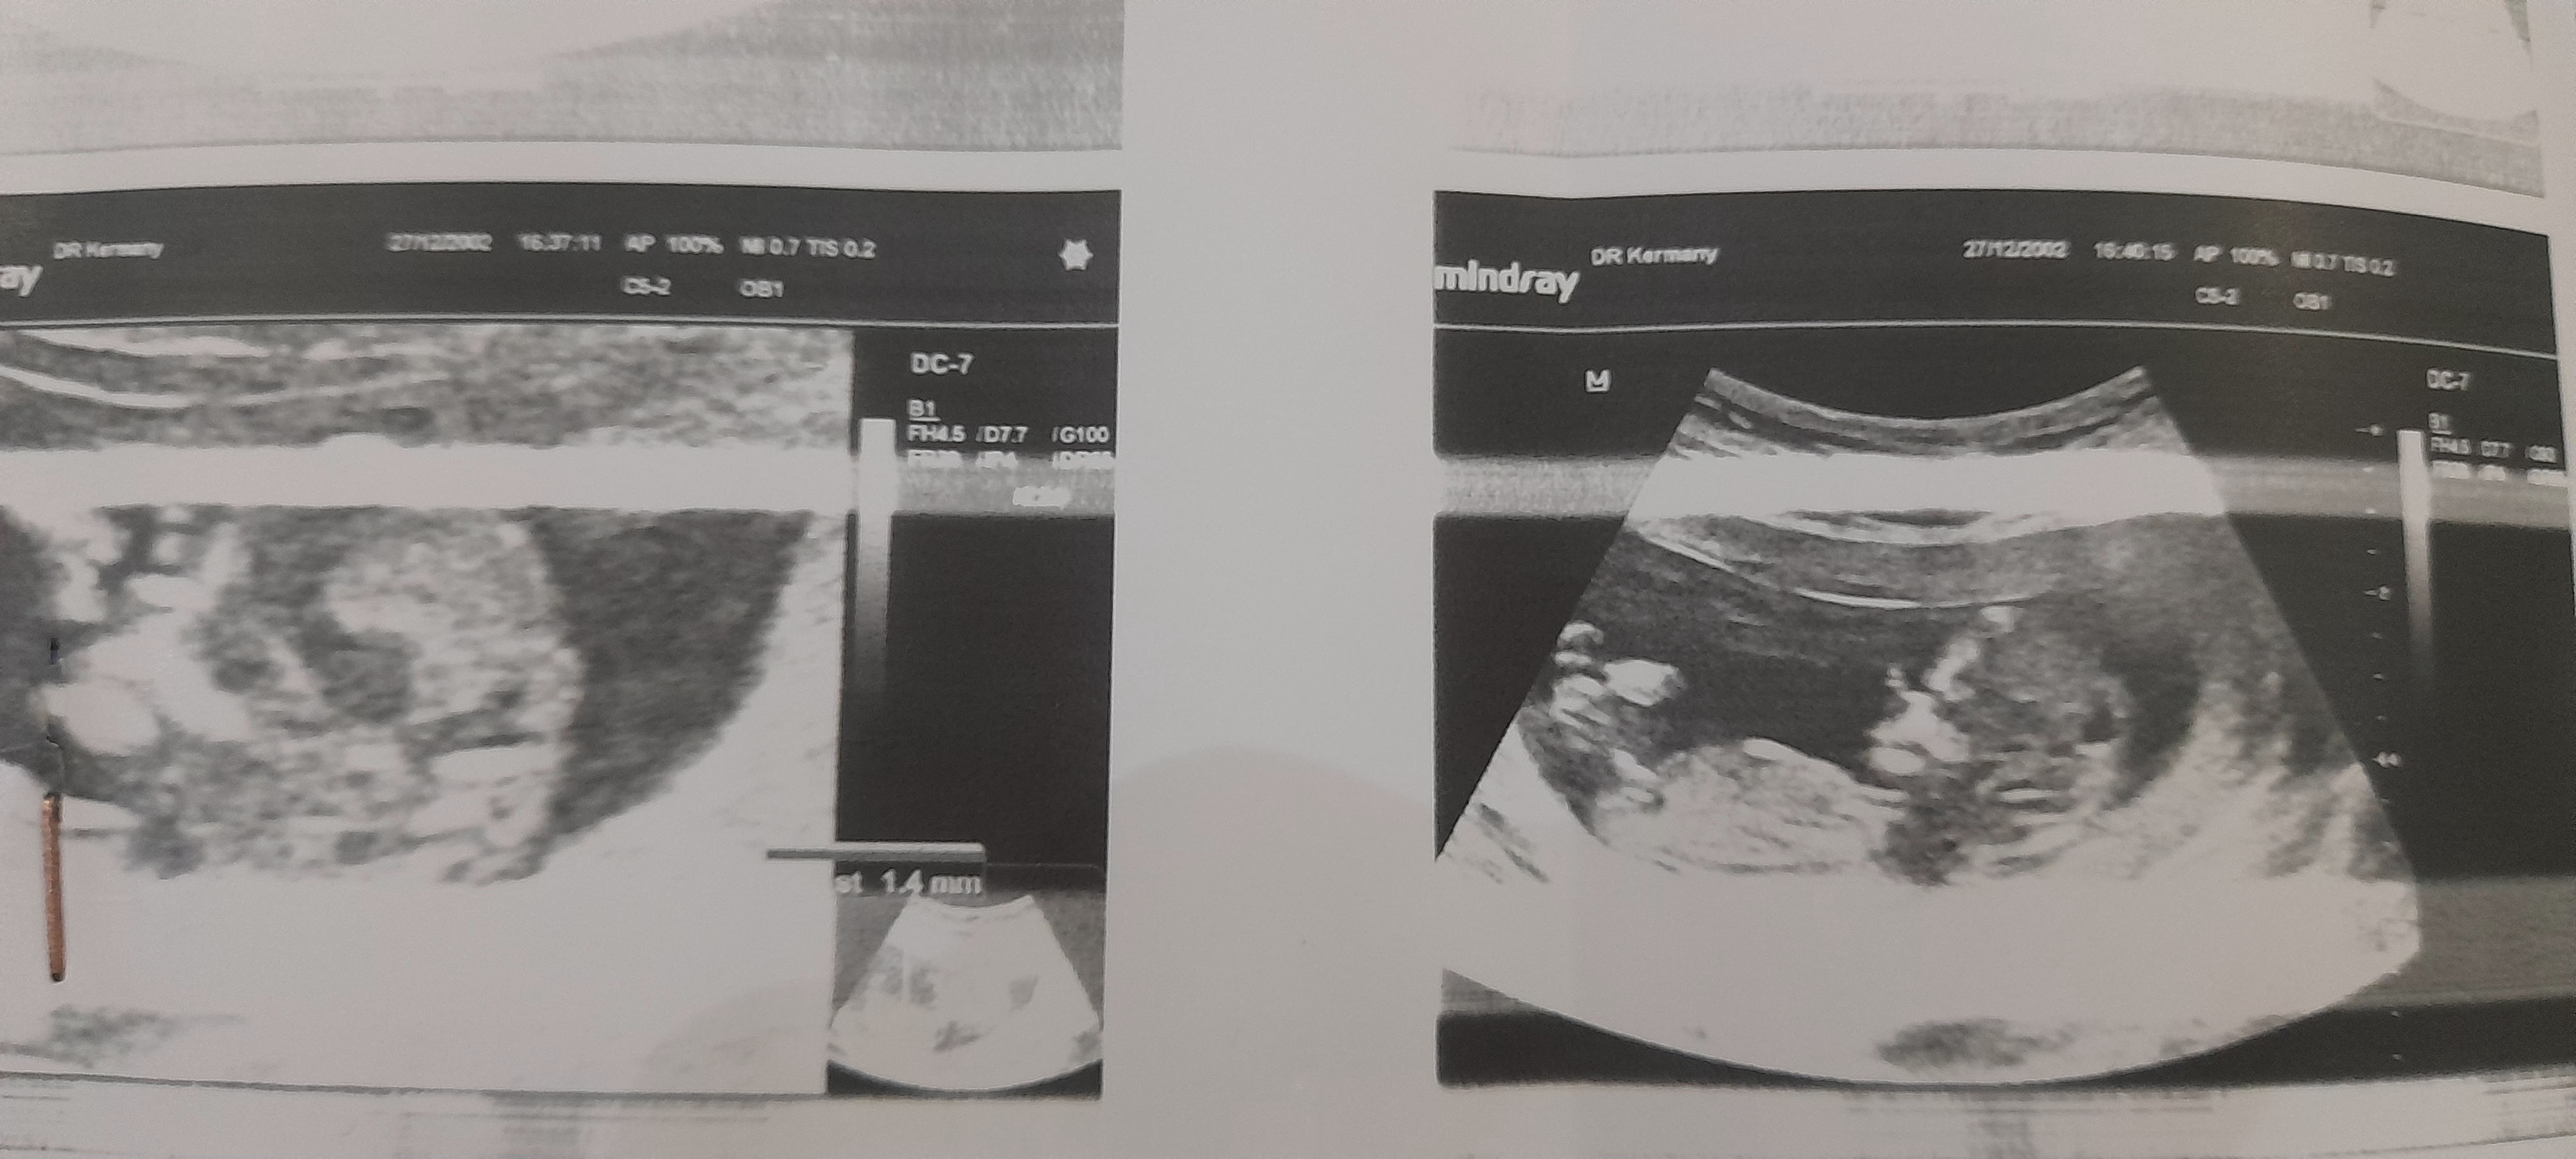

لیموترشش عضویت: 1398/04/12 تعداد پست: 4666 شیطون ببین تو اون چند دقیقه چقدر خودش تکون داده به فاصله ۲ تا عکس انداختن خدایا شکرت بابت همه نعمت هایی دادی . بنظرم هیچ کدوم از نعمت های خدا کوچیک نیستن فقط کافیه به نبودن همون نعمتی که فکر میکنیم کوچیکه بیشتر فکر کنیم

faemeh51 مدیر استارتر عضویت: 1402/10/28 تعداد پست: 44 به نظرم پسره بهت احتمال چی داد؟ دکتر بی اعصاب بود🤣